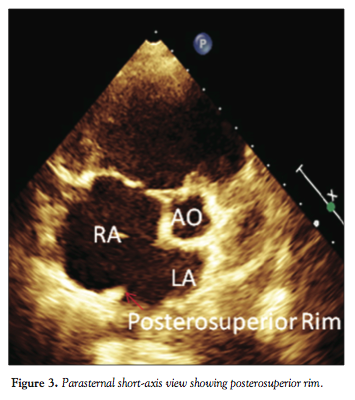

Forty-eight consecutive patients from the outpatient department (OPD) who fulfilled the inclusion criteria were included in the study population. A detailed two-dimensional TTE (Philips IE-33) was

performed using standard protocol for the measurement of defect size, its rims, and total septal length, along with the associated lesions in different views (Figures 1, 2, 3, and 4).

Exclusion criteria. We excluded the following: (1) patients >5 years old with secundum ASD; (2) ASD associated with other complex cardiac malformation; (3) ASD with partial anomalous pulmonary venous connection; (4) multifenestrated ASD; and (5) inadequate rims (posterosuperior, posteroinferior, and anteroinferior rim <4 mm).